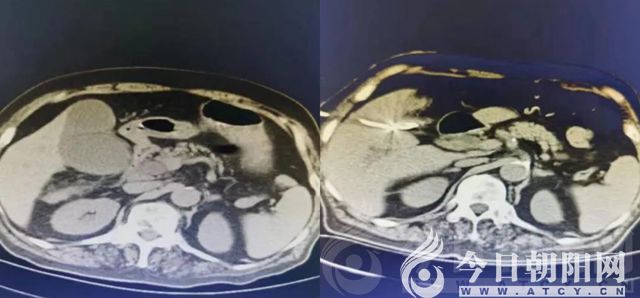

90歲男性患者郭某,既往糖尿病、膽系結(jié)石病史多年。于醫(yī)院內(nèi)分泌科住院治療期間,突發(fā)腹痛、寒戰(zhàn)高熱,腹部CT檢查提示為膽道梗阻,膽囊結(jié)石,膽總管末端結(jié)石,轉(zhuǎn)入普外二科進一步治療。

考慮到患者高齡、基礎(chǔ)疾病復(fù)雜、手術(shù)耐受能力差,做膽囊切除+膽道探查的傳統(tǒng)手術(shù)風險大,醫(yī)院建議急診行經(jīng)皮肝膽囊穿刺或經(jīng)皮肝膽管穿刺引流術(shù),待病情穩(wěn)定后,擇期處理原發(fā)病?;颊呒覍俦硎纠斫?。手術(shù)過程順利,患者腹痛緩解,尿量增多,體溫趨于正常。1周后帶管出院。